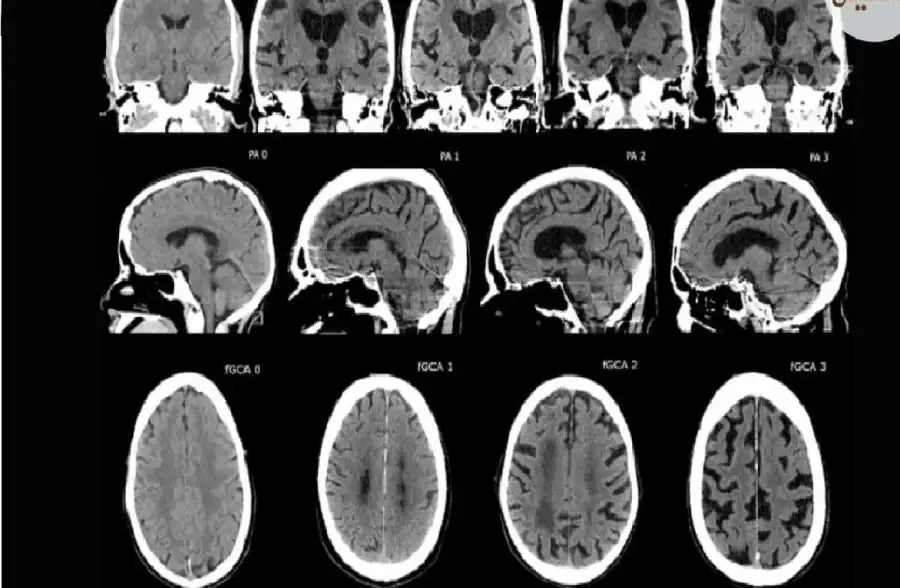

ويشير هولمز إلى ظاهرة "الضمور المعرفي" التي بدأت تظهر حتى في المهن الدقيقة مثل طب الأشعة، حيث أظهرت دراسة من كلية الطب بجامعة هارفارد أن المساعدة التي يقدمها الذكاء الاصطناعي، رغم أنها تحسن أداء البعض، إلا أنها قد تضر بمهارات التشخيص لدى آخرين لأسباب لا تزال غير مفهومة تماماً.